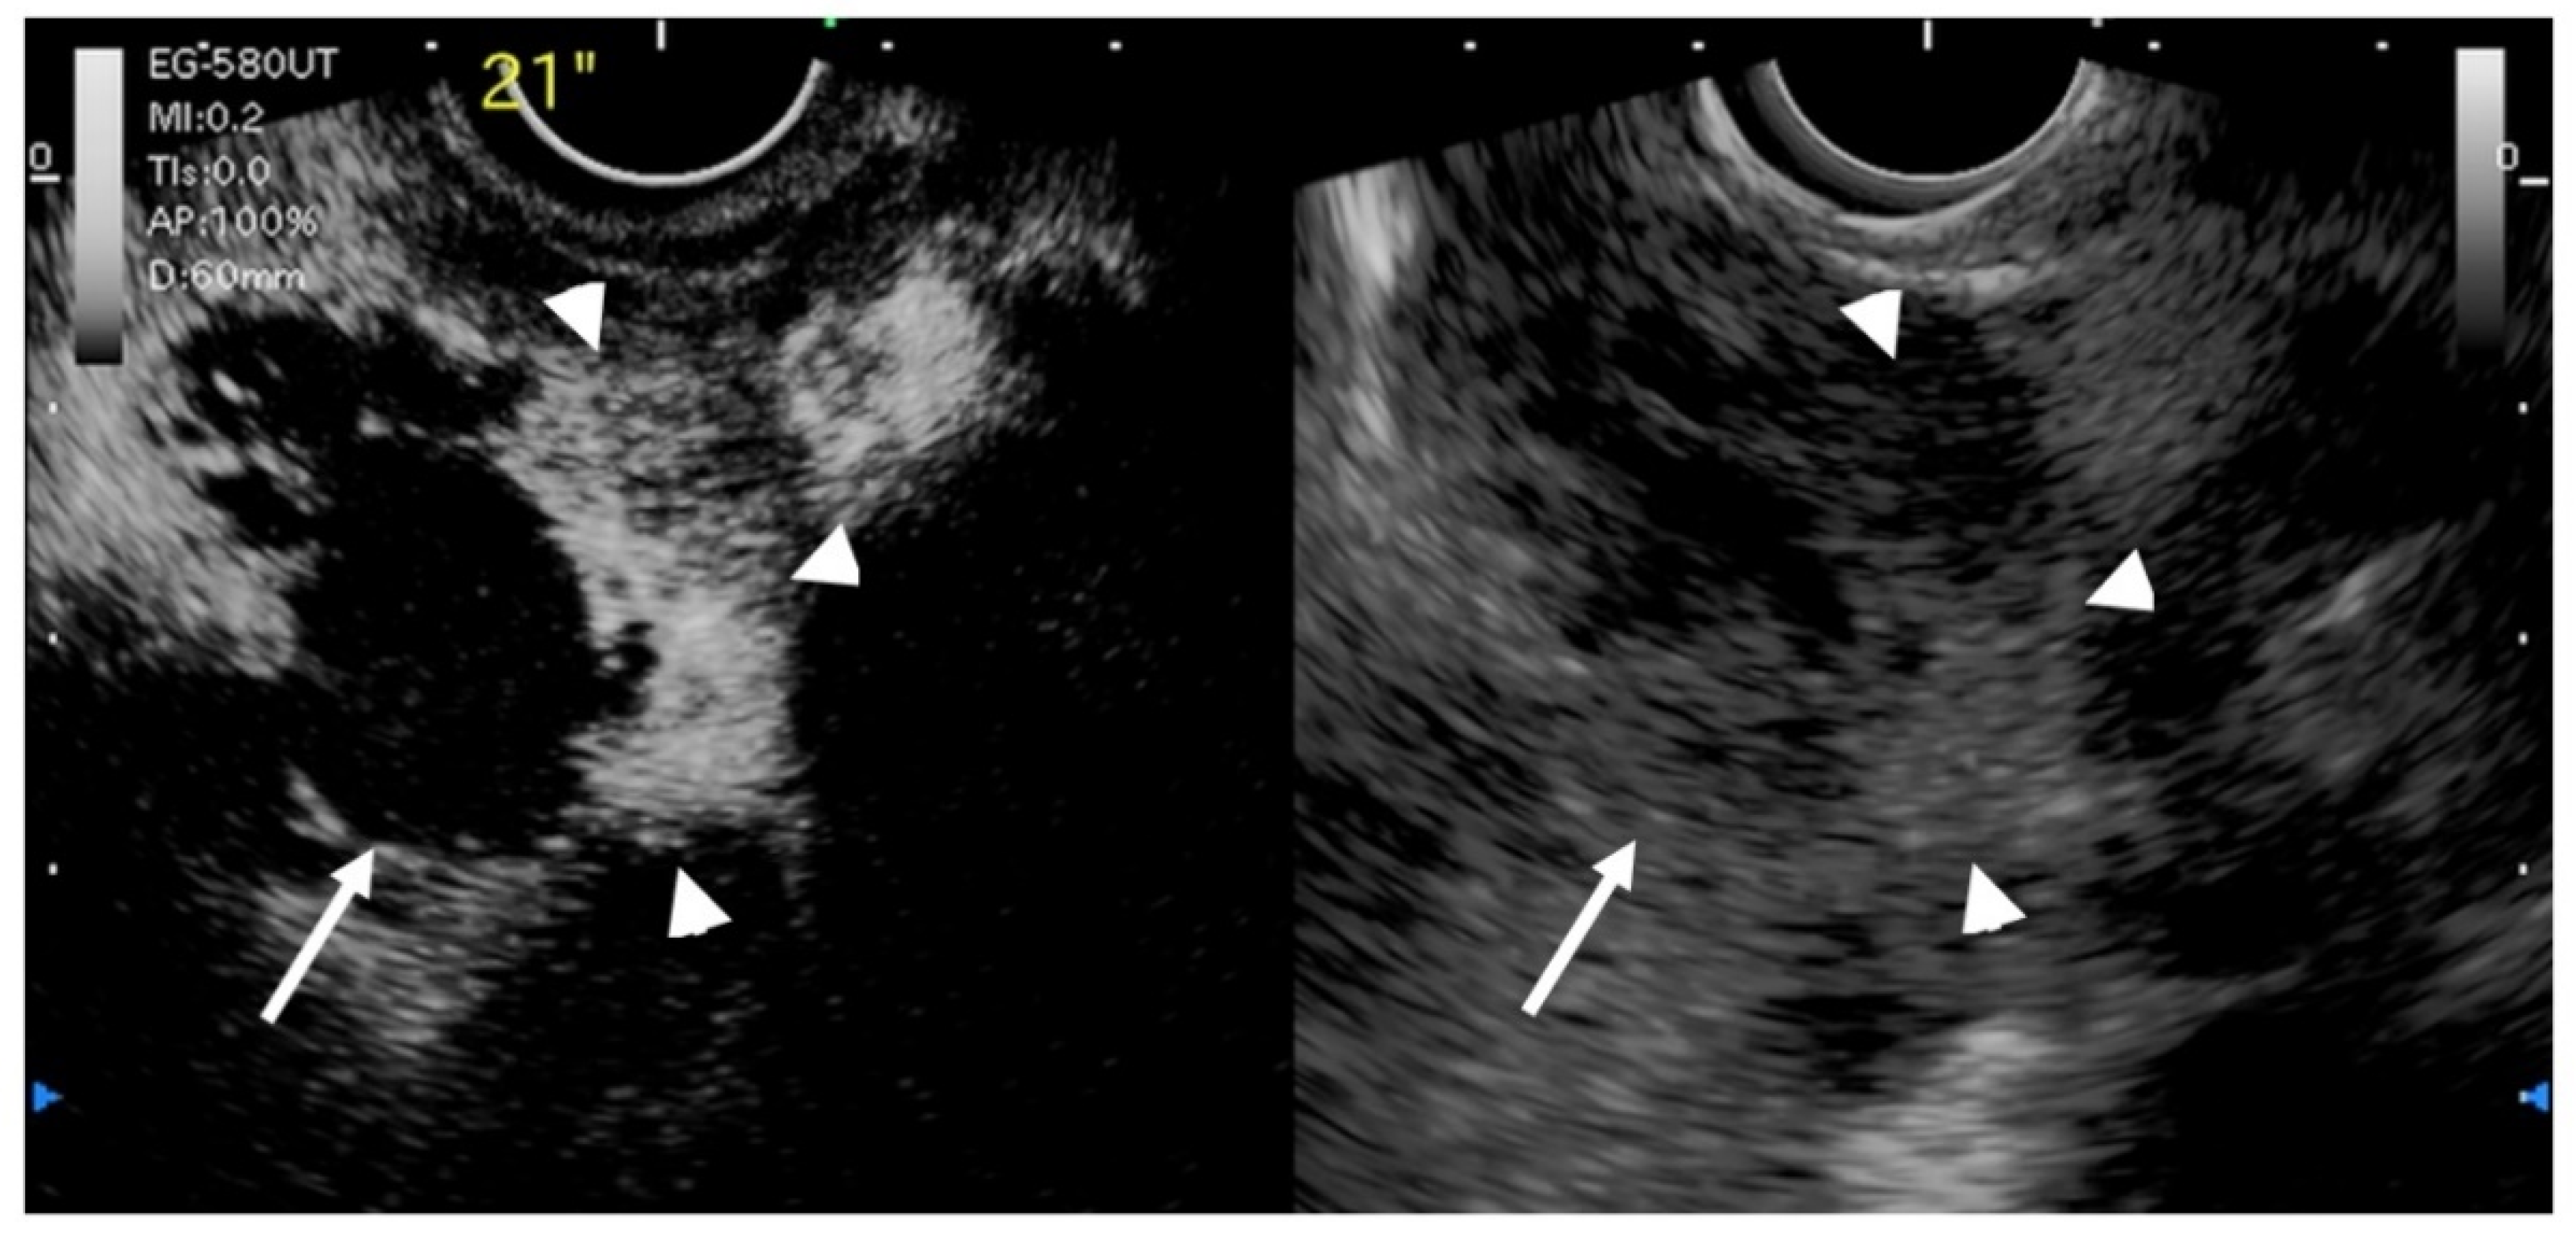

- Hirooka, Y.; Naitoh, Y.; Goto, H.; Ito, A.; Hayakawa, S.; Watanabe, Y.; Ishiguro, Y.; Kojima, S.; Hashimoto, S.; Hayakawa, T. Contrast-enhanced endoscopic ultrasonography in gallbladder diseases. Gastrointest. Endosc. 1998, 48, 406–410. [Google Scholar] [CrossRef]

- Choi, J.H.; Seo, D.W.; Choi, J.H.; Park, D.H.; Lee, S.S.; Lee, S.K.; Kim, M.H. Utility of contrast-enhanced harmonic EUS in the diagnosis of malignant gallbladder polyps (with videos). Gastrointest. Endosc. 2013, 78, 484–493. [Google Scholar] [CrossRef] [PubMed]

- Kamata, K.; Takenaka, M.; Kitano, M.; Omoto, S.; Miyata, T.; Minaga, K.; Yamao, K.; Imai, H.; Sakurai, T.; Nishida, N.; et al. Contrast-enhanced harmonic endoscopic ultrasonography for differential diagnosis of localized gallbladder lesions. Dig. Endosc. 2018, 30, 98–106. [Google Scholar] [CrossRef] [Green Version]

- Imazu, H.; Mori, N.; Kanazawa, K.; Chiba, M.; Toyoizumi, H.; Torisu, Y.; Koyama, S.; Hino, S.; Ang, T.L.; Tajiri, H. Contrast-enhanced harmonic endoscopic ultrasonography in the differential diagnosis of gallbladder wall thickening. Dig. Dis. Sci. 2014, 59, 1909–1916. [Google Scholar] [CrossRef]

- Sugimoto, M.; Takagi, T.; Konno, N.; Suzuki, R.; Asama, H.; Hikichi, T.; Watanabe, K.; Waragai, Y.; Kikuchi, H.; Takasumi, M.; et al. The efficacy of contrast-enhanced harmonic endoscopic ultrasonography in diagnosing gallbladder cancer. Sci. Rep. 2016, 6, 25848. [Google Scholar] [CrossRef]

- Leem, G.; Chung, M.J.; Park, J.Y.; Bang, S.; Song, S.Y.; Chung, J.B.; Park, S.W. Clinical Value of Contrast-Enhanced Harmonic Endoscopic Ultrasonography in the Differential Diagnosis of Pancreatic and Gallbladder Masses. Clin. Endosc. 2018, 51, 80–88. [Google Scholar] [CrossRef] [Green Version]

- Liang, X.; Jing, X. Meta-analysis of contrast-enhanced ultrasound and contrast-enhanced harmonic endoscopic ultrasound for the diagnosis of gallbladder malignancy. BMC Med. Inform. Decis. Mak. 2020, 20, 235. [Google Scholar] [CrossRef]